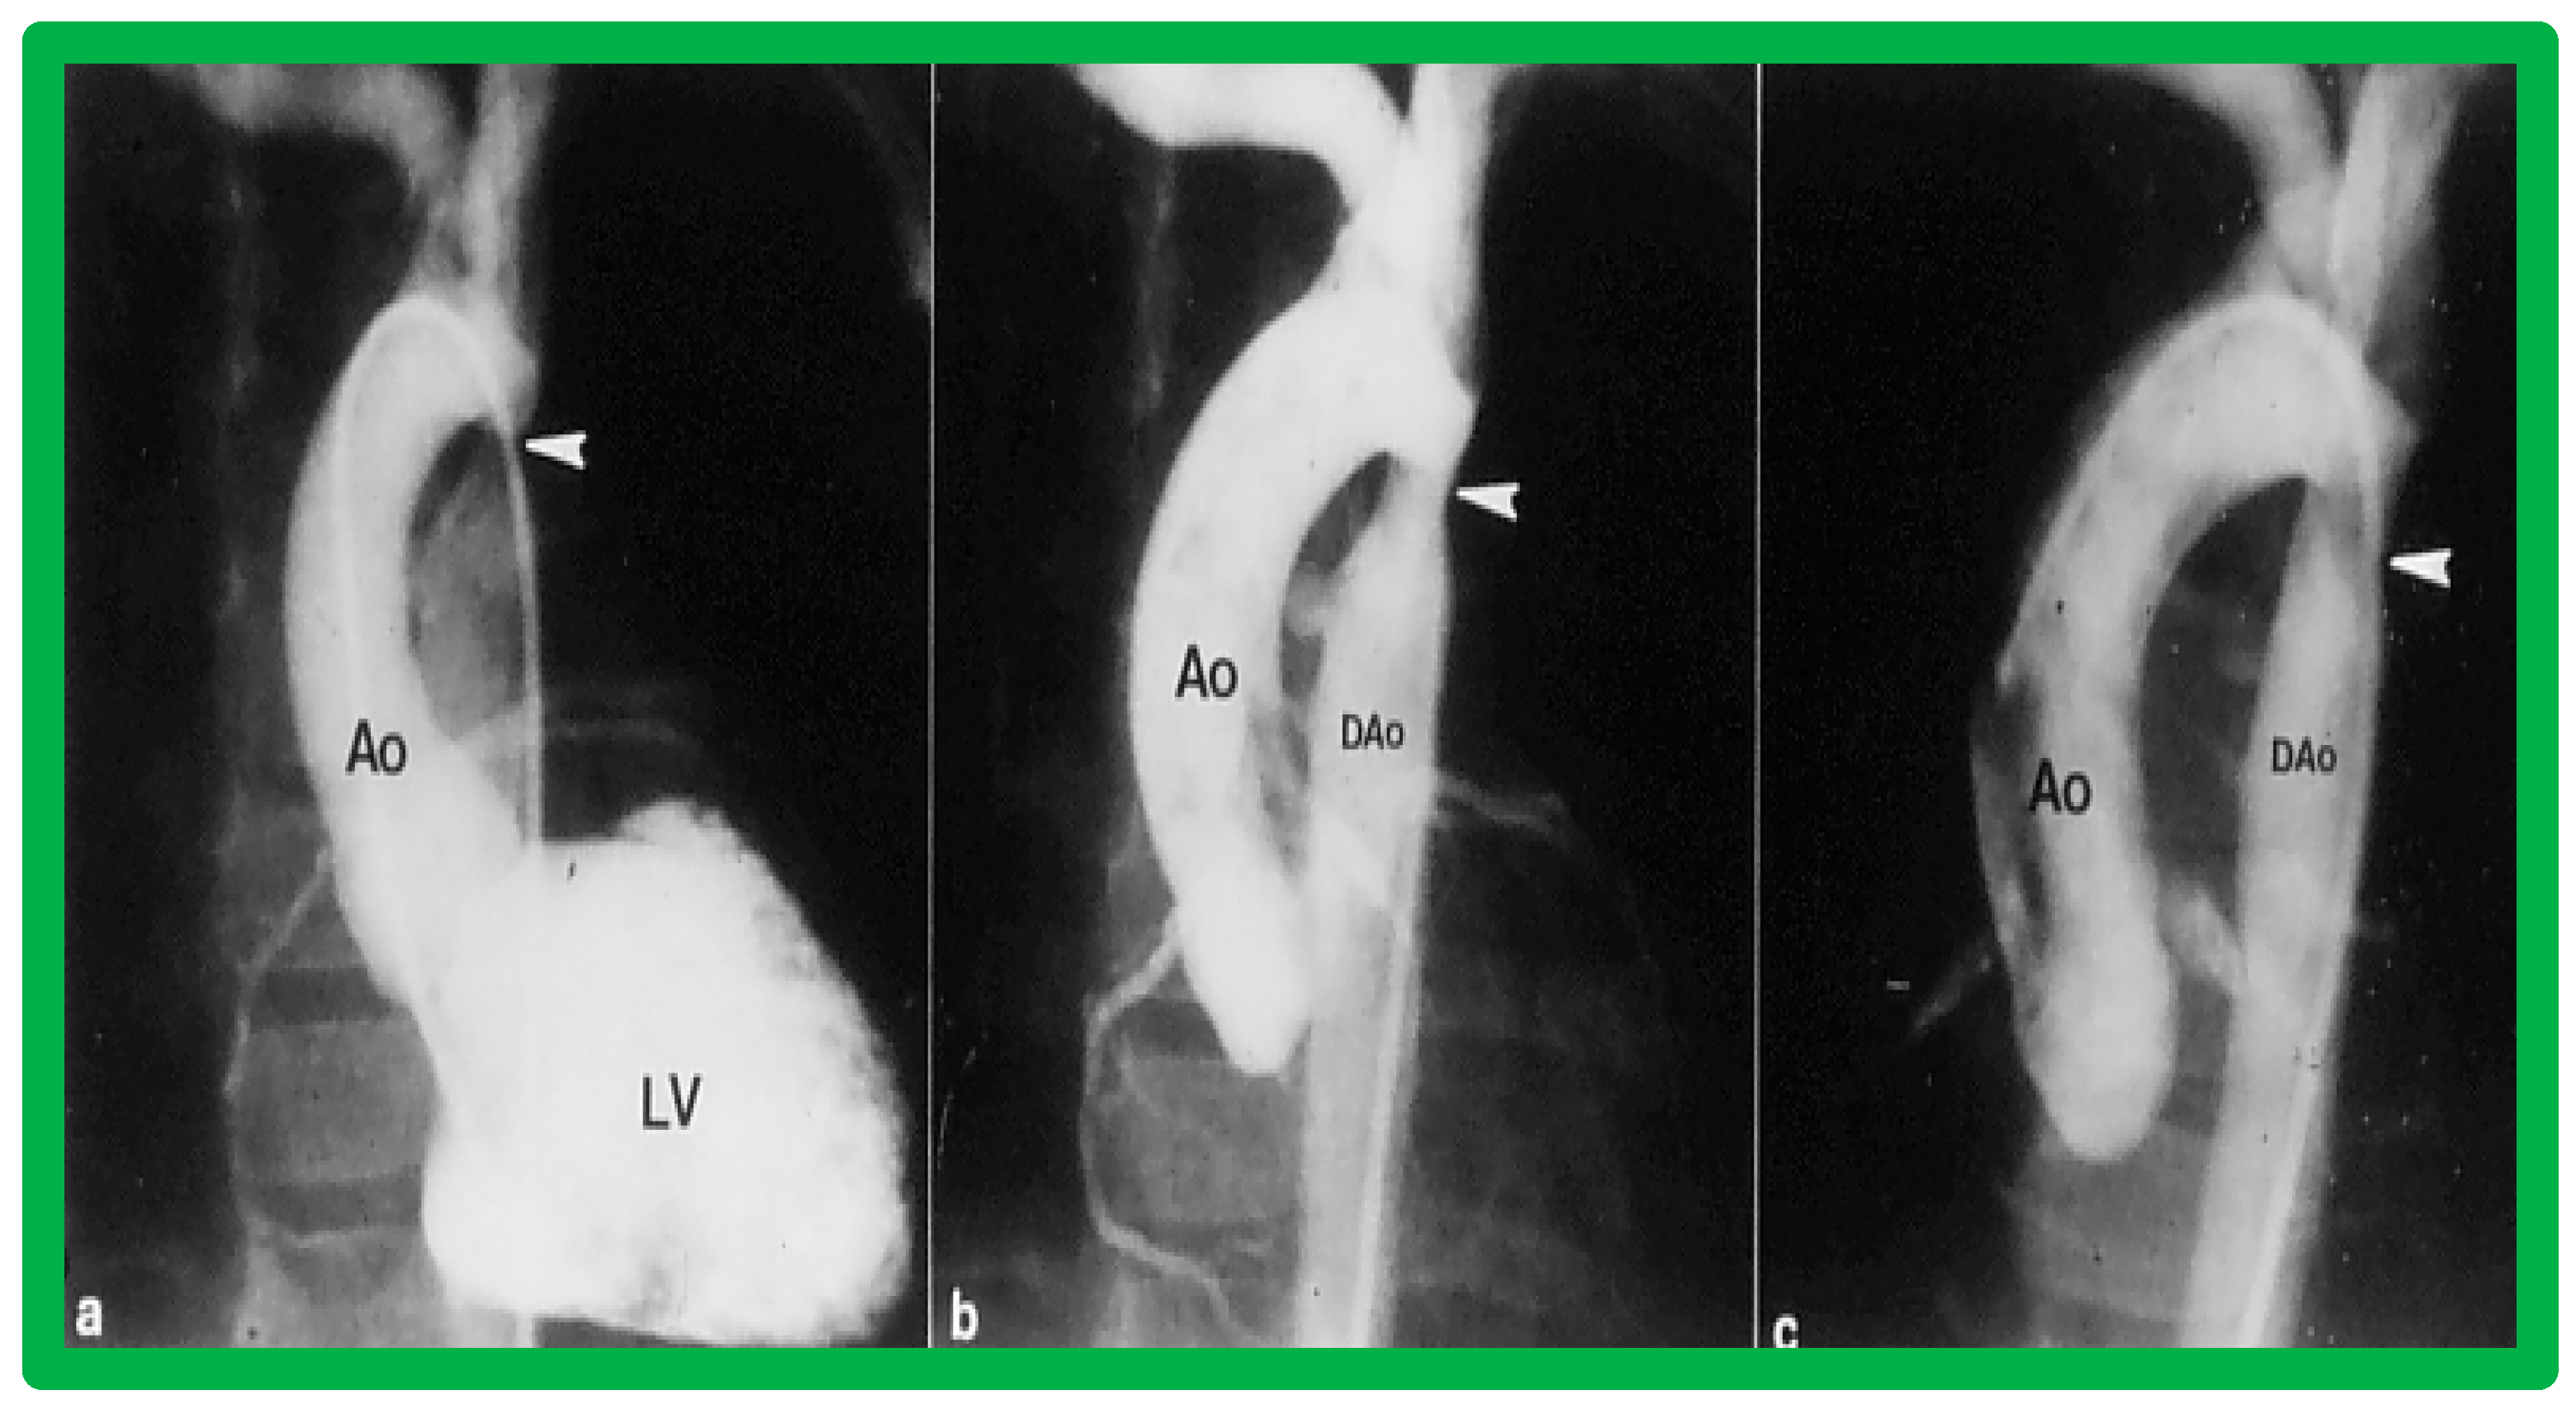

3.2. Aortic Stenosis

4.2. Aortic Stenosis